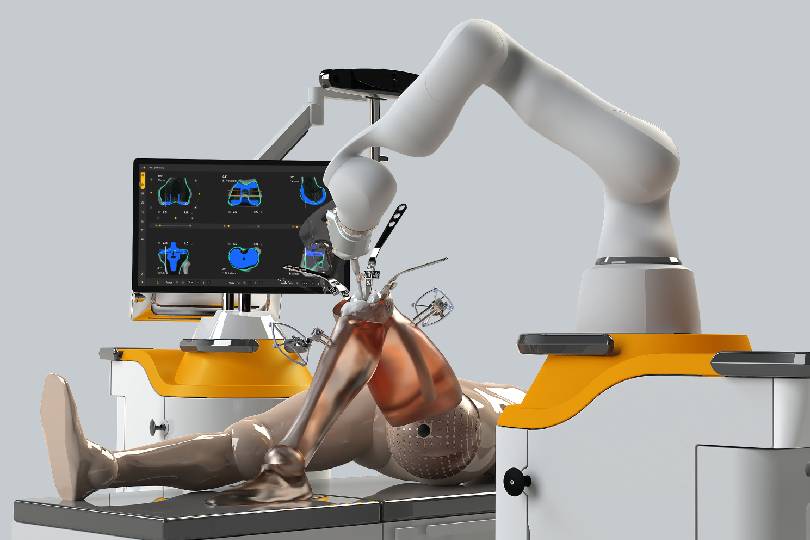

Robotic Joint Replacement

Imagine a world where mobility is limited due to joint pain and stiffness, where everyday tasks become daunting challenges.

Robotic Joint Replacement uses advanced robotic-assisted technology for enhanced precision in implant placement and alignment. This leads to improved joint function, less pain, minimal tissue damage, and quicker rehabilitation compared to conventional methods.

In Robotic Knee Replacement, a robotic system assists the surgeon in planning and executing the procedure with extreme accuracy. Benefits include smaller incisions, faster recovery, reduced postoperative pain, and a more natural knee movement after surgery.

Yes. Robotic-assisted surgeries are safe and highly precise. The robotic system doesn’t operate on its own; it assists the surgeon with detailed mapping and positioning, ensuring the best possible surgical outcomes with fewer complications.